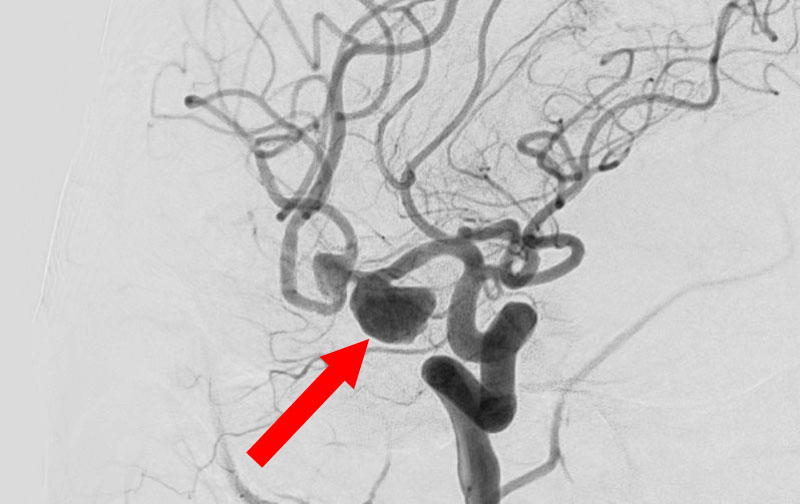

No.1630 手術前